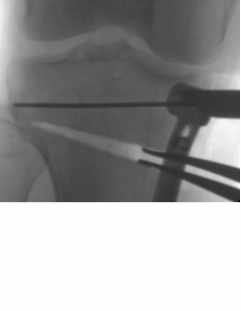

Before the plate is applied, laminar spreaders force the wedge open. The amount is opening will have been calculated from computerised imaging assessments before the procedure.